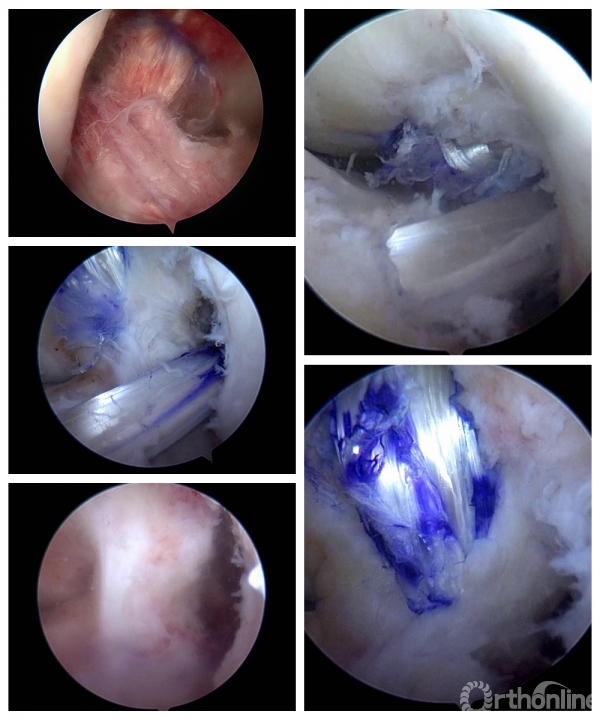

真知灼见,术台见功夫——手术直播

本次会议的重点是手术实时在线直播,在随后的时间里陆续进行。专家们分组轮流进行手术演示。术者根据病情展示各自的独特手术技巧,现场观摩的医生可以即时与术者及其他观摩者交流学术思路,全程互动,有任何疑问随时与术者交流。

在两天的会议中,成功完成了11台手术,包括4台膝关节韧带重建、2台膝关节内侧骨关节炎单髁置换、1台肩关节前方复发性不稳定改良Bristow稳定术,1台巨大肩袖撕裂SCR修补、1台肩肩胛下肌冈上肌撕裂修补、1台跟腱痛风性腱病伴撕裂清理修补、1台距骨骨囊肿关节镜下清理植骨。

△手术名称:肩关节前方复发性不稳定改良Bristow稳定术 术者:崔国庆教授

△手术名称:前后交叉韧带重建 术者:李箭教授、张文涛教授(三台手术)

△手术名称:巨大肩袖撕裂 上关节囊重建 术者:丁少华教授

△手术名称:肩胛下肌、冈上肌撕裂修补 术者:李瑾教授